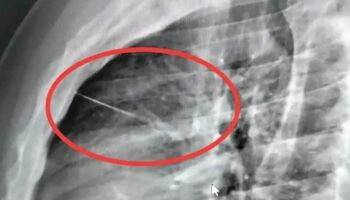

19.05.2026Таиланд НовостиДоставщик в Бангкоке сбит поездом рядом с местом недавней смертельной аварииКурьер по доставке еды получил тяжелые травмы после того, как его сбил поезд, пока он мочился

19.05.2026Таиланд НовостиThailand Новости | Британские перевозчики наркотиков становятся мишенью для банд, базирующихся в Таиланде, Бангкок выбран для гранд-финала песенного конкурса Евровидение в Азии Сегодня мы’ дадим вам некоторые обновления о ситуации с крушением поезда, включая предоставление